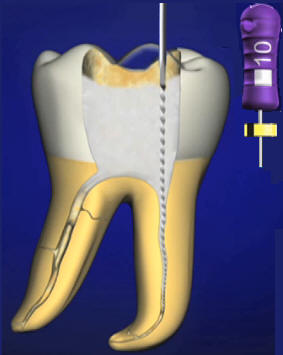

Fresas de

Gates Glidden

El

ensanchador Gates Glidden tiene un extremo

cortante corto, en forma de llama, con hojas

cortantes laterales levemente espiraladas

con ángulo muy inclinado respecto de la

vertical. Generalmente tiene una pequeña

guía no cortante en su extremo para

minimizar su potencial de perforación de la

superficie radicular. Ver imagen

izquierda

La cabeza

cortante está conectada al vástago por un

fino y largo cuello. Está numerado del 1 al

6 mediante marcas en el tallo del

instrumento. Se utilizan para la ampliación

y conformación de los conductos después del

limado seriado y ensanchamiento con limas,

en sus tercios cervical y a veces hasta el

tercio medio. Ver imagen derecha